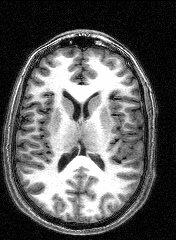

The images to the right are virtual 'slices', taken horizontally, starting from the top and working down. Cerebrospinal fluid is dark, the white matter appears light.